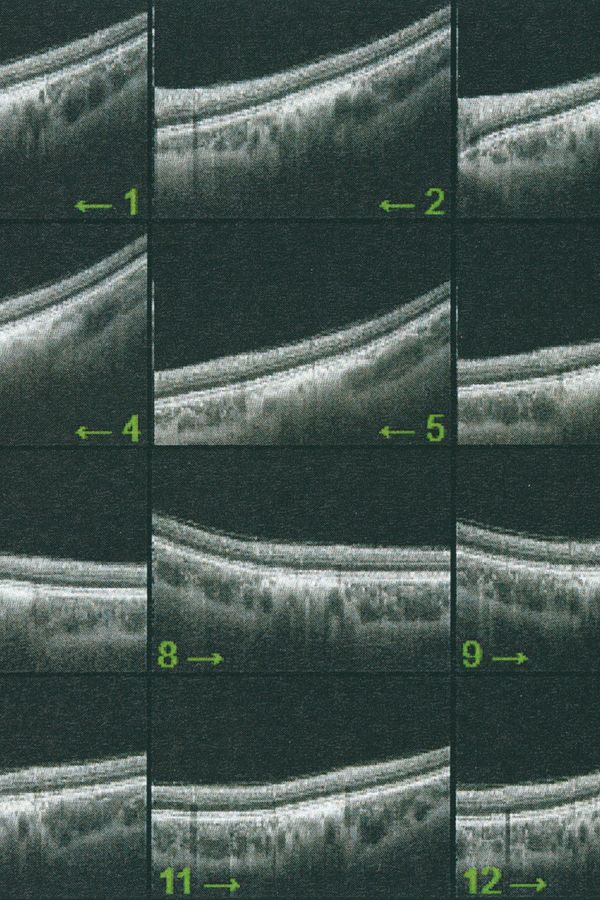

Collirio is an exercise in comparison. On the one hand, there is the cut left from my lisergic experience, on the other the one described by Lacan, analogue and yet still of opposite function.

The project navigates between these two cuts, attempting to reconnect vision and visuality on a common ground. It seeks to link a personal condition to the more collective one of the gaze, of the images that constitute its archaeology, of abstraction, of the delocalization of the point of view and of the fragmentation of its experience. The acrid smell of vinegar syndrome fills the boxes of reels and rolls. Lucanae are like tired arms, at the end of which is a hand whose grip on meaning has loosened. We are no longer able to grasp it firmly with the same strength. The emulsion begins to separate from its support. The reality of images is no longer able to embody its indexical value as a trace with the same efficacy. Thus, the truth of meaning stops before the surface, unable to emerge. It lingers behind the fiber of a paper sheet, behind the light of a black screen, between the zeroes and the ones of a circuit.